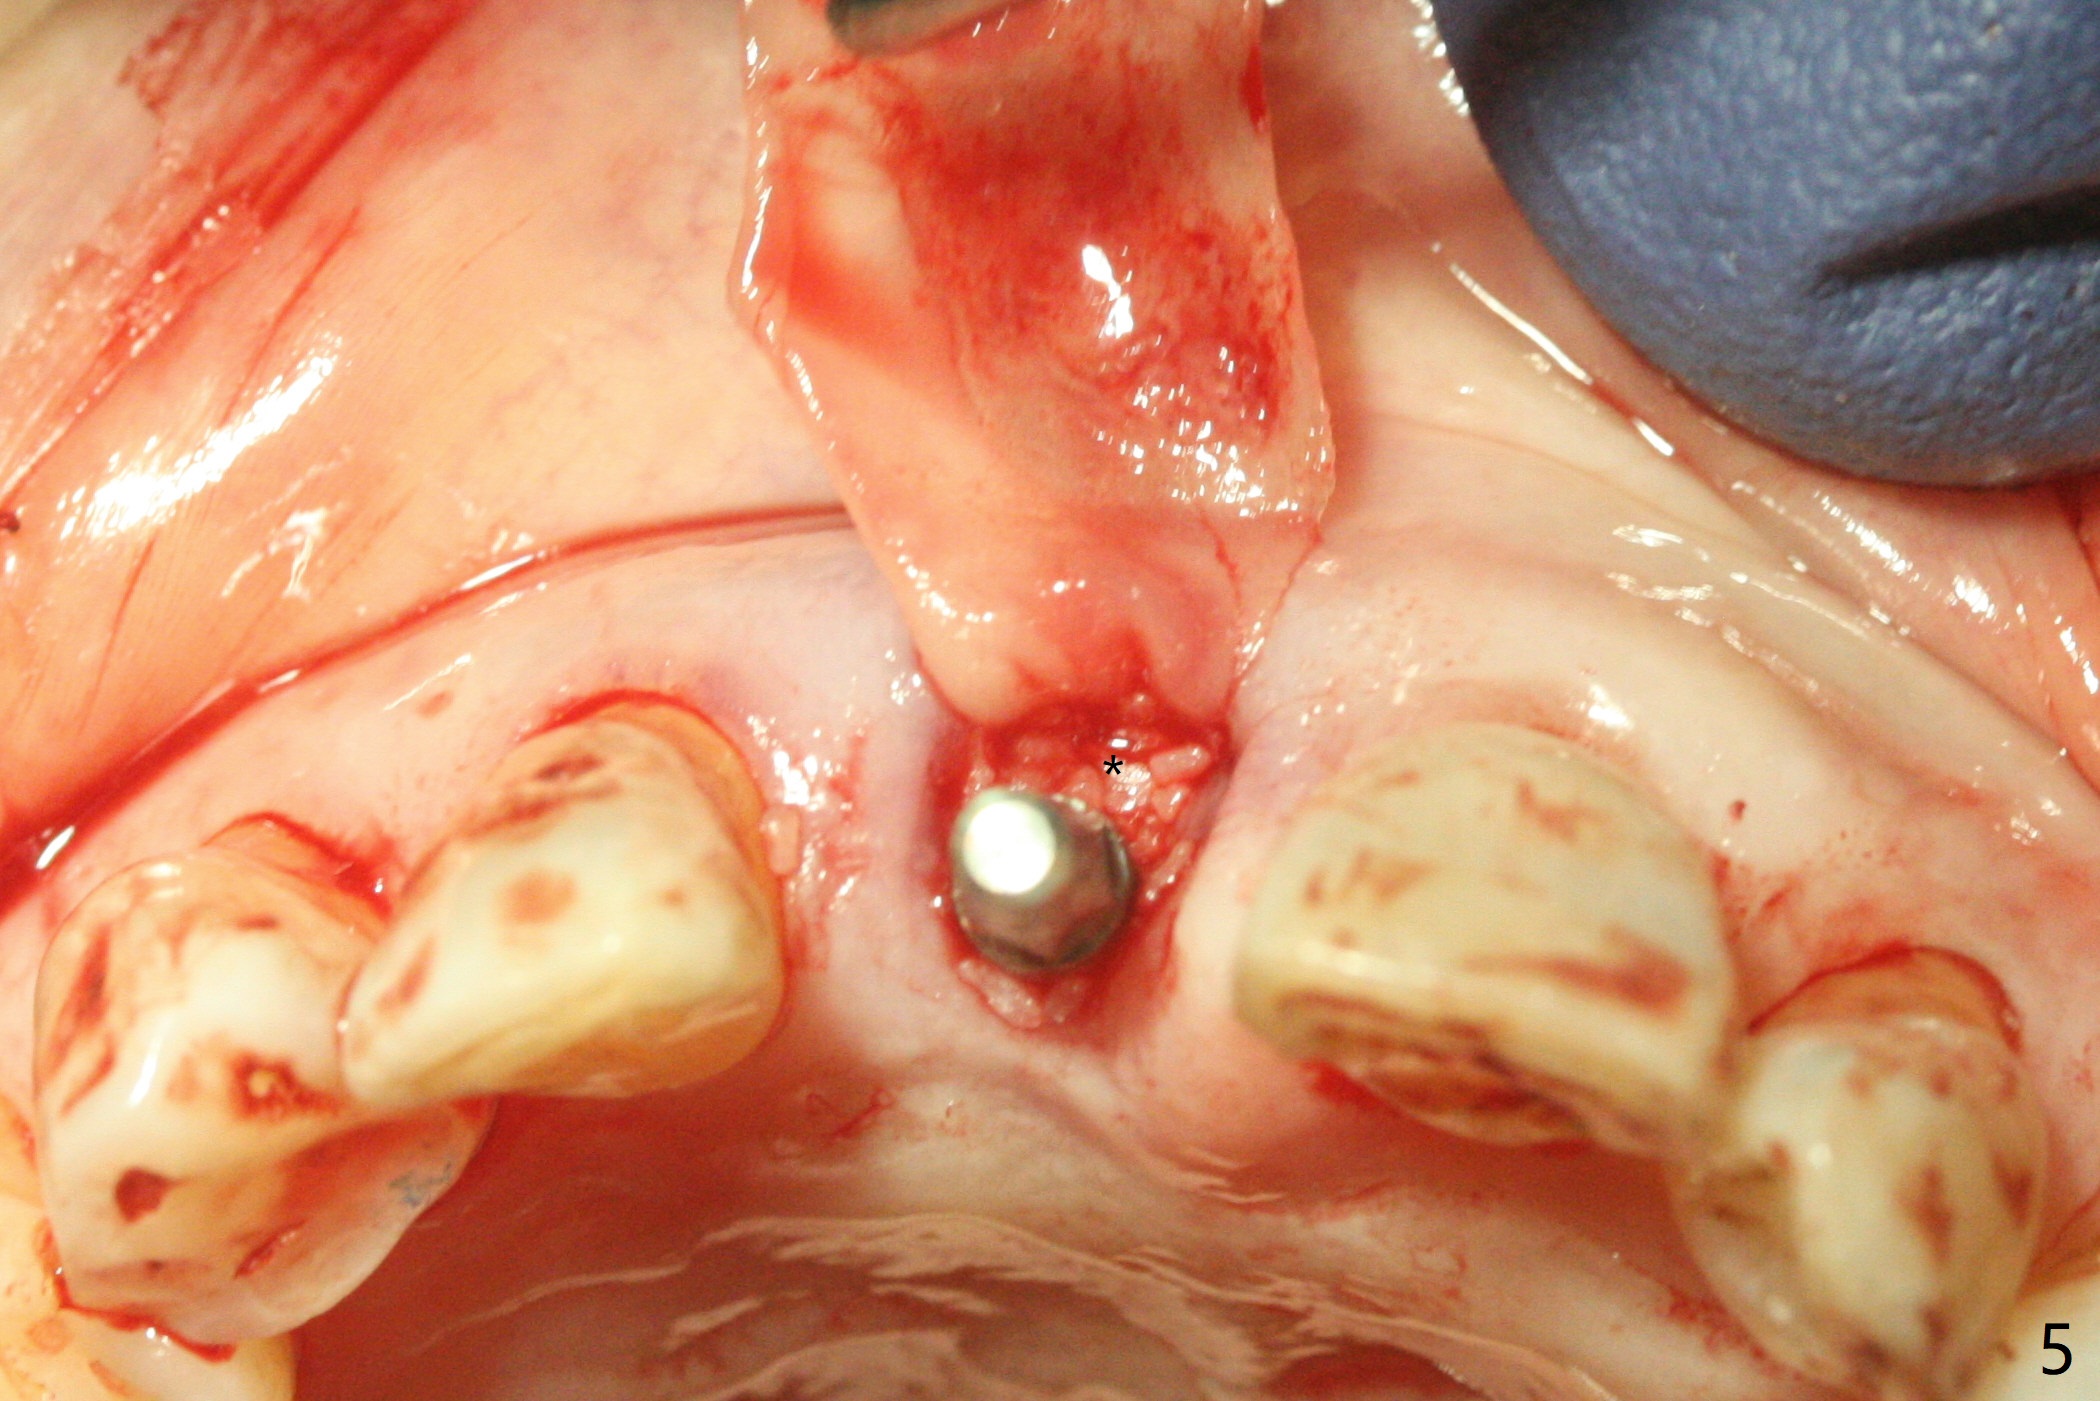

59岁女术前右下1,2切缘磨短后,右上1颊侧移位得到纠正(图一(咬合创伤))。拔牙后证实颊侧骨板缺失,钻洞始于腭侧(图二),当1.5毫米钻头感觉刚穿破鼻底时,置入2.5x14(4)毫米一段式植体,好像进入鼻腔,但是扭力<10Ncm(图三)。把一张PRF膜放入牙槽窝,一端紧贴颊侧牙龈腭侧,另一端放置颊侧牙龈颊侧(图四),然后开始用粘性骨粉(图五,七:*(100%皮质骨))充填颊侧间隙。后者填满时(图五:*),将外面一端PRF翻转覆盖牙槽窝开口,并插入基台固定(图六),最后插入龈下,用临时牙冠固定(图八(T),九(*:PRF))。术后九天牙龈退缩(图十:^),临时牙冠突出(*),后者龈缘和切缘进行调整,缩短(图十一,十二),少许骨粉暴露(图十二:>),十四天后牙龈往下生长,好像形成角化龈(图十三:*)。